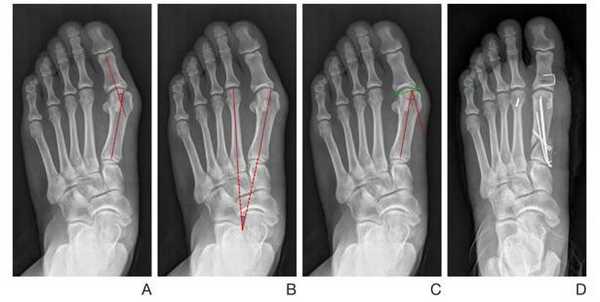

Операция при плоскостопии у взрослого: поперечное — продольное, показания, виды, результаты

В ортопедии выделяют продольный и поперечный своды стопы. Первые располагаются вдоль ступни и поддерживаются мышечно-связочным аппаратом. Основную роль в укреплении этих сводов играет длинная подошвенная связка. Именно ее пластику чаще всего выполняют в случае развития продольного плоскостопия.

Поперечный свод стопы образован головками I-V плюсневых костей. В норме они образуют своеобразную арку. Поперечный свод поддерживается связками, сухожилиями и головкой мышцы, приводящей большой палец стопы. При нарушении мышечно-связочного баланса у человека возникает поперечное плоскостопие. Как правило, оно осложняется вальгусной деформацией I пальца стопы.

Рентген плоской стопы.

По статистике, Hallux Valgus разной степени выявляют у 100% пациентов с поперечным плоскостопием. Во время хирургического вмешательства врачам приходится одновременно устранять обе патологии.

Показания и цели хирургического лечения

Основные принципы оперативного лечения плоскостопия:

- Дифференцированный подход, учет степени деформации и вариабельности анатомо-функционального строения стопы.

- Устранение всех компонентов плоскостопия и исключение их повторного появления в будущем.

- Прочное соединение костных структур с целью ранней активизации пациентов и восстановления подвижности пальцев.

- Обязательно сохранение всех точек опоры (пяточная кость, головки I и V плюсневой кости) при лечении разных видов плоскостопия.

Фото до и после операции.

Операция при продольном плоскостопии

Когда возникает необходимость коррекции продольного плоскостопия, врачи делают операции на внутренней и/или задней части стопы. При слабовыраженной деформации они выполняют пластику связок и сухожилий. В более тяжелых случаях им приходится делать операции на костях предплюсны.

Таблица 1. Особенности разных видов хирургических вмешательств.

Факт! Лицам старше 30 лет артродез делать не рекомендуется из-за риска развития стойкого болевого синдрома.

Медиализирующая остеотомия пяточной кости в сочетании с таранно-ладъевидным артродезом.

Не так давно ученые провели исследование и выяснили, какие методики наиболее эффективны в лечении продольного плоскостопия. Лучшим методом коррекции оказалась медиализирующая остеотомия пяточной кости в сочетании с таранно-ладъевидным артродезом. Она дает хороший клинический результат и редко приводит к осложнениям. В отличие от подтаранного артродеза, после такого лечения больному не требуется повторное хирургическое вмешательство.

О слабости связочного аппарата говорит появление так называемого «эластичного плоскостопия». Для патологии характерно уплощение свода стопы при ходьбе. В состоянии покоя ступни приобретают нормальный вид.

Операции при поперечном плоскостопии

Лечение комбинированного типа

Поперечно-продольное плоскостопие - это наиболее тяжелая форма заболевания. У человека деформируются сразу оба свода, а стопа становится абсолютно плоской. Лечить патологию довольно тяжело.

Цели операций при комбинированном плоскостопии:

- восстановление сводов стопы;

- надежная неподвижная фиксация костей;

- исправление деформаций I пальца;

- удаление экзостозов;

- коррекция молоткообразной деформации.

Операция продольно-поперечной деформации.

При поперечно-продольном плоскостопии человеку делают сразу несколько вмешательств. Например, больному одновременно выполняют операцию Шеде, остеотомию Scarf и артродезирование некоторых суставов плюсны. Как правило, врачи стараются сделать все за одно хирургическое вмешательство.

Восстановительный период после таких операций длится дольше, чем в остальных случаях. К счастью, пациентам не требуется гипс или костыли. В худшем случае им придется походить с фиксирующими спицами, которые снимут вместе со швами уже через 2 недели.